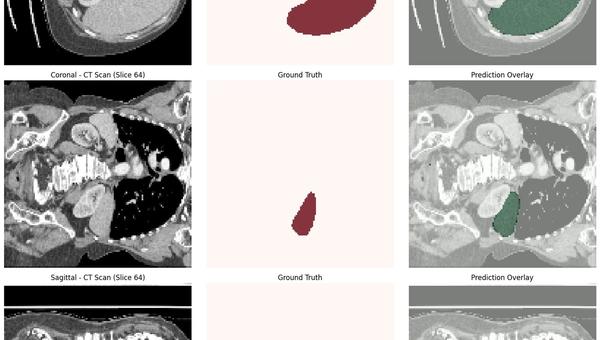

This was my first experience working with a large-scale 3D medical imaging dataset. The MSD Task03 Liver dataset is over 25GB, and training a full 3D model required designing a strong backend pipeline for data preprocessing, batching, and sliding-window inference. Training the model for ~160 epochs on my local RTX 3060 (12GB), and the system achieved a 95.6% Dice score. SwinUNETR captures long-range anatomical dependencies better than CNNs. What the system does: 1. Reads and processes full 3D abdominal CT volumes 2. Standardizes orientation (RAS), voxel spacing, intensity ranges, and crops foreground 3. Uses a 3D Vision Transformer (SwinUNETR) for segmentation 4. Handles inference using MONAI’s sliding-window engine and produces accurate 3D liver masks that can be downloaded as NIfTI files What I built: 1. A fully modular preprocessing pipeline (orientation, cropping, resizing) 2. An optimized training loop with Dice loss, mixed precision, checkpointing, and metric tracking 3. A complete evaluation script for volume-wise Dice scoring 4. A trained SwinUNETR model that generalizes well on held-out test CT volumes